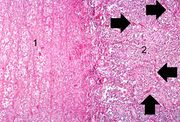

| 03:22, 19 August 2013 | IPLab3Bronchopneumonia3.jpg (file) | 28 KB | Seung Park | This is a low-power photomicrograph of lung with multiple focal lesions (1) throughout the tissue, some of which have a pale center indicating a loss of parenchymal tissue (2). This is typical of abscess formation in the lung and represents a form of l... | 1 | |